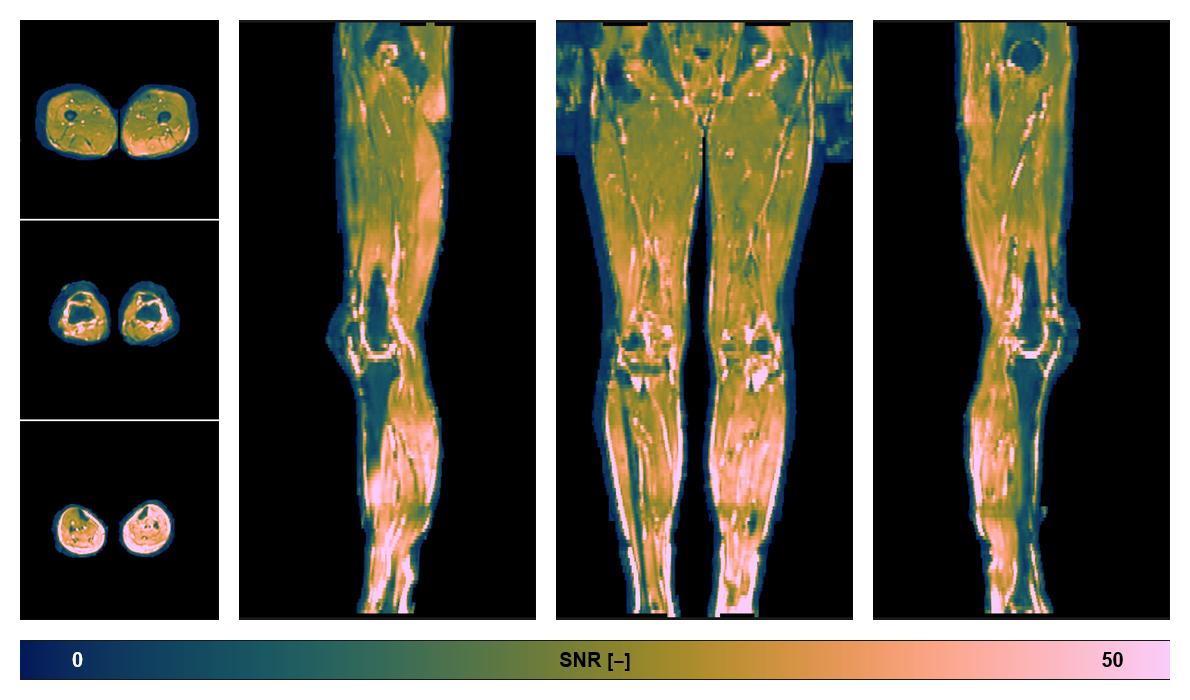

• SNR of the unweighted image

SNR distribution of the unweighted diffusion data.